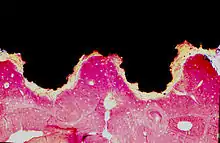

Exemple d'ostéointégration : coupe histologique microscopique d'un os intégré à la surface en titane d'un implant dentaire (en noir)

Appliqué à l'implantologie orale, on parle d'intégration de l'implant dentaire dans l'os sans tissu mou interposé. Aucun cartilage ou ligament ne sont présents entre l'os et la surface de l'implant.